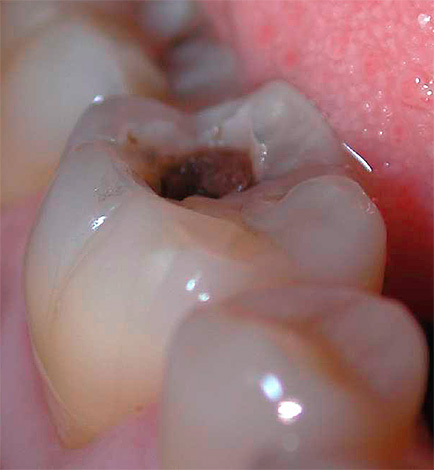

La foto seguente mostra carie delle fessure, cioè localizzato nell'area del sollievo naturale dei denti. Sotto tale oscuramento, i tessuti significativamente distrutti sono spesso nascosti all'interno, che non vengono immediatamente rilevati durante un esame di routine:

A casa, una tale "carie interna" è quasi impossibile da rilevare. Si rilascia solo con un esteso danno alla dentina e la comparsa di dolore al dente quando la polpa è inclusa nel processo patologico. Ecco perché le visite profilattiche dal dentista sono così importanti che metodi speciali possono rilevare la carie in qualsiasi sua localizzazione e curare il dente prima che sia necessario rimuoverlo (rimozione del nervo).